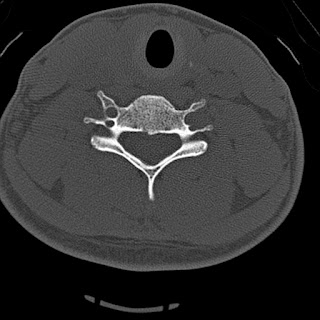

The Castellvi system for organizing lumbosacral variations.

Useful only for classification, not prognostic significance. |